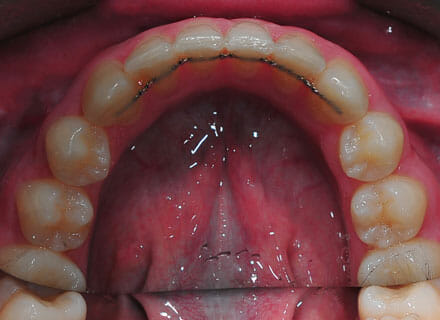

This lady hated her very uneven smile, all the teeth sticking out at the sides, teeth bunched together and uneven. We fitted clear brackets and a wire on the inside in the upper jaw in the roof of the mouth and in under 18 months the teeth were perfectly aligned and the patient’s smile was changed forever.